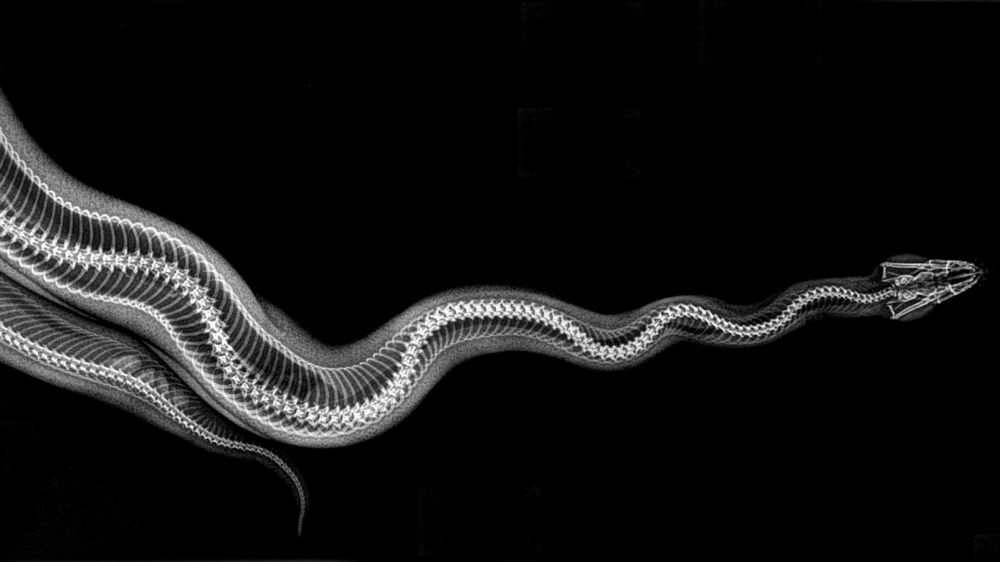

ABD'nin Oregon eyaletinde bulunan bir hayvanat bahçesi, hayvanların rutin sağlık kontrolleri sırasında çekilen X-Ray görüntülerini paylaştı.

Sağlık kontrolleri sırasında bazı hayvanlara röntgen çektiklerini söyleyen hayvanat bahçesi yetkilileri, bu yöntem sayesinde sağlık değerlendirmelerinin daha kolay yapıldığını ifade etti.